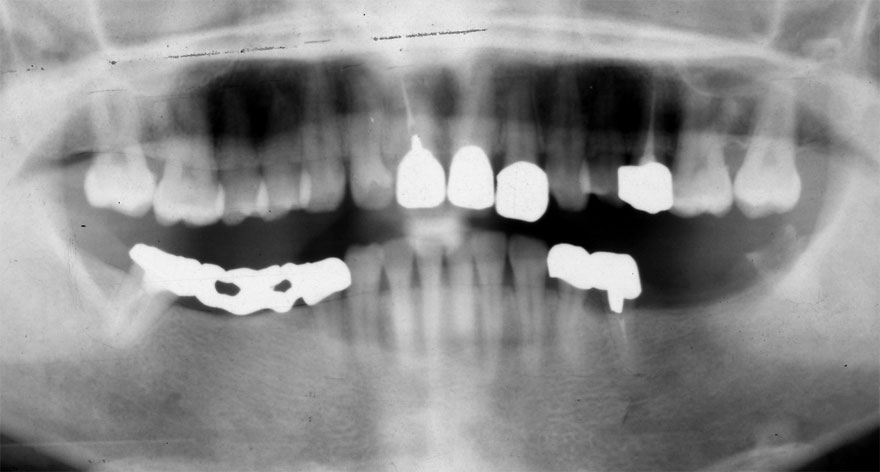

開始年齢 30代

初診時 30歳 女性 平均歯槽骨喪失量:1.46mm

22年後 52歳

平均歯槽骨喪失量:1.55mm

22年間喪失量:-0.09mm

年間喪失速度:-0.004mm

(ケア頻度:1.76ヵ月ごと)